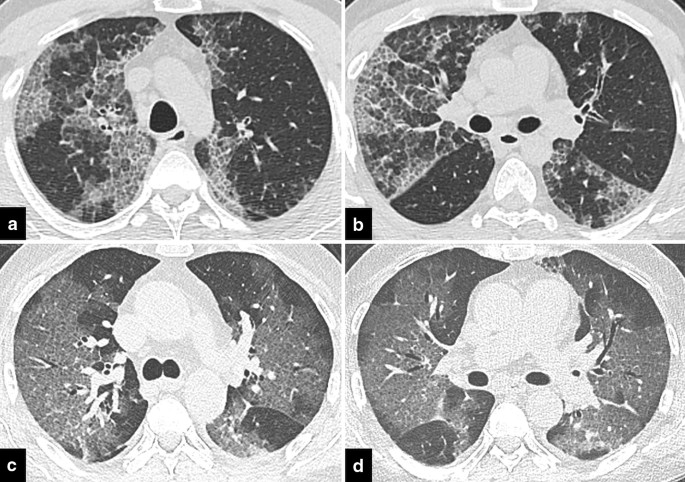

Focal GGOs or opacities with rounded morphology may be encountered in COVID-19 pneumonia [10]. In the presence of focal GGOs, neoplastic processes should also be considered. Preinvasive lesions (atypical adenomatous hyperplasia and adenocarcinoma in situ), early-stage adenocarcinoma (Fig. 7), and multifocal adenocarcinoma (Fig. 8) may have variable imaging features, such as pure GGOs, GGOs in combination with consolidation, nodules surrounded by a halo of GGO (CT halo sign), and GGOs with crazy-paving pattern. Air bronchograms in larger lesions, pleural effusion, and lymphadenopathy can be seen [34,35,36,37]. Similarly, mucinous adenocarcinoma metastases can manifest as focal or multifocal GGOs, consolidations, and nodules with a CT halo sign [38, 39]. Besides tumoral growth, CT halo sign can represent peritumoral hemorrhage in hemorrhagic metastases such as angiosarcoma [17] (Fig. 9).

COVID-19 pneumonia-mimicking multifocal adenocarcinoma of the lung. a, b Multiple randomly distributed GGOs with superimposed septal thickening in both lungs, histopathologically proven to be adenocarcinoma. c, d Multiple GGOs in a COVID-19 patient with rounded morphology and superimposed septal thickenings mimicking multifocal adenocarcinoma